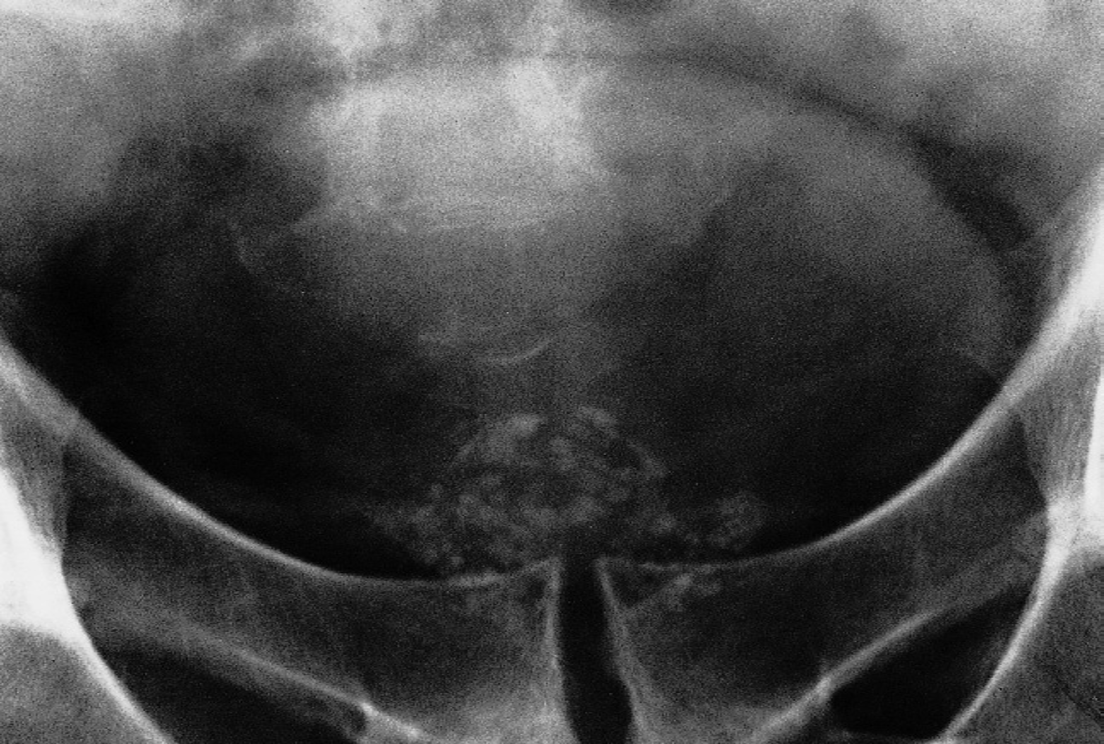

Flecks of calcification of varying size, approximately symmetrical about the midline, are seen just inferior to the bladder.